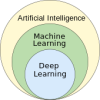

One burgeoning application is the use of AI in interpreting medical images – a field that relies on deep learning, a sophisticated form of machine learning in which a series of labelled images are fed into algorithms that pick out features within them and learn how to classify similar images. This approach has shown promise in diagnosis of diseases from cancers to eye conditions.